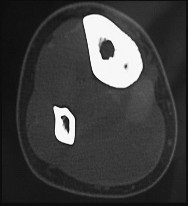

A 24-year-old male presents with a slow-growing, painful soft tissue mass around the knee. Core needle biopsy reveals a biphasic tumor with both spindle cells and epithelial cells. What is the characteristic cytogenetic abnormality associated with this pathology?

Explanation

The patient has a biphasic synovial sarcoma. Synovial sarcoma is uniquely characterized by the t(X;18)(p11;q11) translocation, which results in the SYT-SSX fusion gene. t(11;22) is characteristic of Ewing sarcoma, t(9;22) is associated with myxoid chondrosarcoma (and CML), t(12;16) is seen in myxoid liposarcoma, and t(2;13) is seen in alveolar rhabdomyosarcoma.